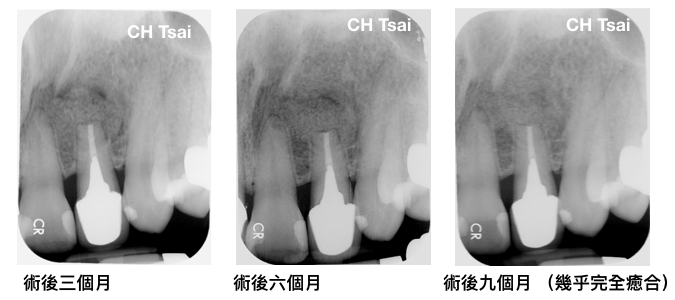

接下來就是期待術後的恢復,何小姐也相當配合的進行回診的追蹤,可以看到以下術後的X光片明顯根尖齒槽骨慢慢的生長,牙根周圍的牙周韌帶也慢慢恢復出現。